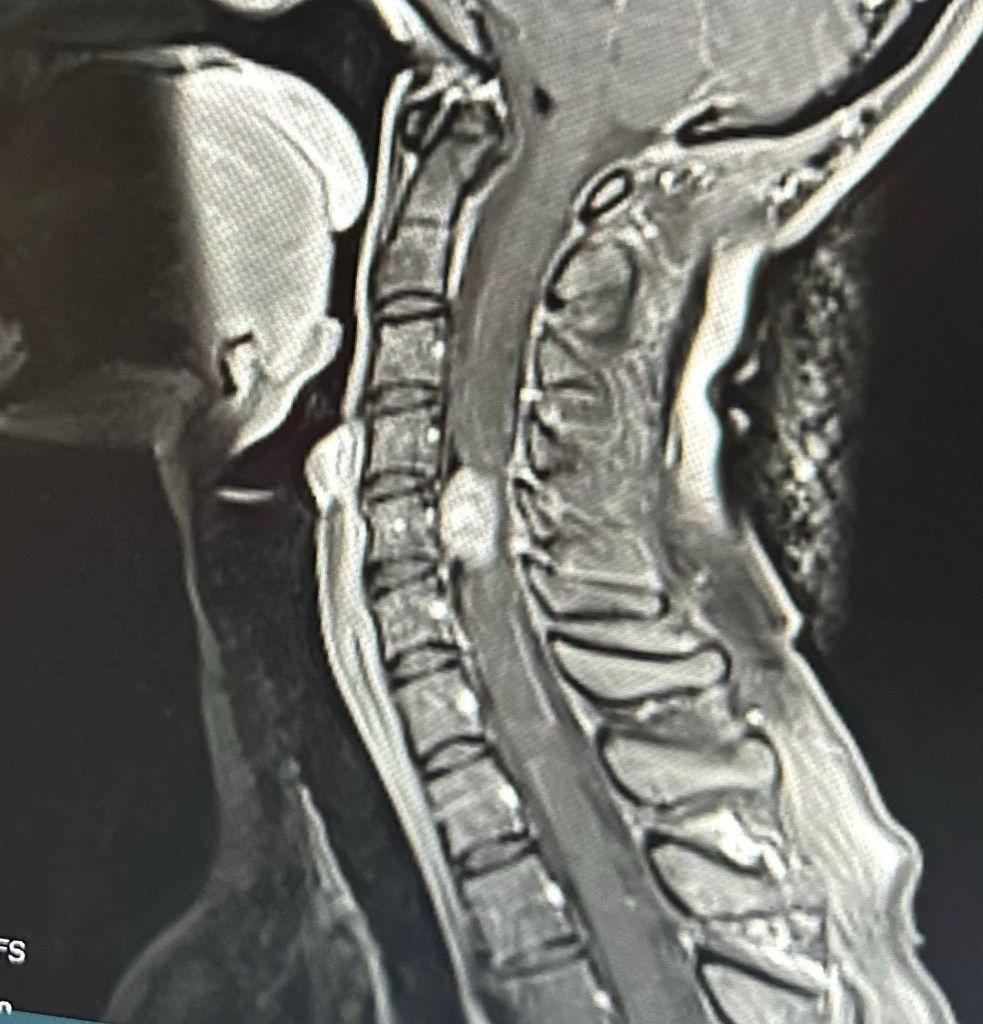

Sagittal view of the tumor (white) in my spine

They checked the brain as well as cervical, thoracic, and lumbar spines for the MRI. Thankfully, aside from the cervical spine, the rest of the MRI looked good! However, between C4 and C6 is a 2.6 x 1.3 x 1.0 cm mass. This mass is pressing on the nearby nerves and displacing the spinal cord, subsequently causing all of the sensory issues and severe pain.

I met with the neurosurgeon yesterday, and the plan is for surgery at Abbott Northwestern this coming Monday. After meeting him, I feel very comfortable with this surgeon. He actually trained at Mayo, and Has experience with LMS! He will have access to state of the art technology during surgery (including neuro monitoring), and I feel confident in his skills. As I feared, since you can’t get wide margins when operating in the spine, I will need radiation after surgery to ā€œclean upā€ any cells that might get left behind. Plans for that are yet to come…